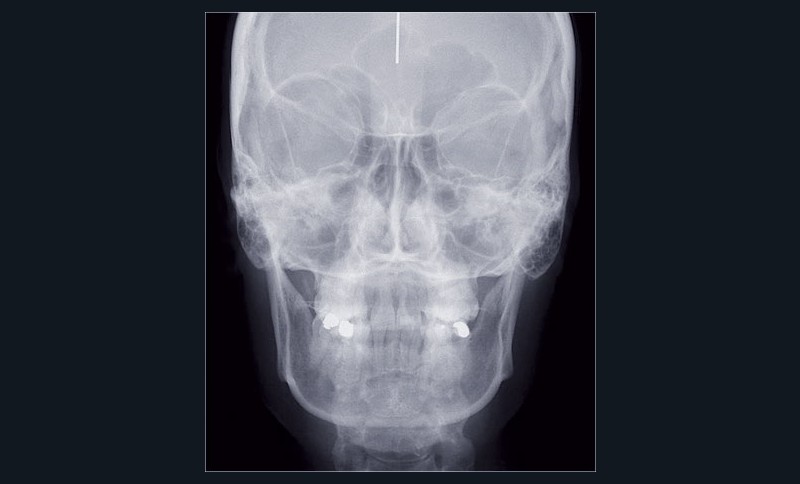

Cas n° 2

Nous lui avons donc proposé un traitement d’alignement avec maintien des 14 et 24 en position de 13 et 23 et optimisation du torque pour favoriser un développement des arcades et chercher à améliorer le sourire et le soutien labial.

Un appareillage Damon métal a été mis en place, réalisé à partir d’un set up numérique Insignia pour obtenir un contrôle précis des torques et de la forme d’arcade et réduire le temps de finition grâce à un collage indirect très précis.

L’objectif, en utilisant la technique Insignia est de réduire le temps de traitement de 28 à 18 mois avec 12 rendez-vous (fig. 5 à 14).